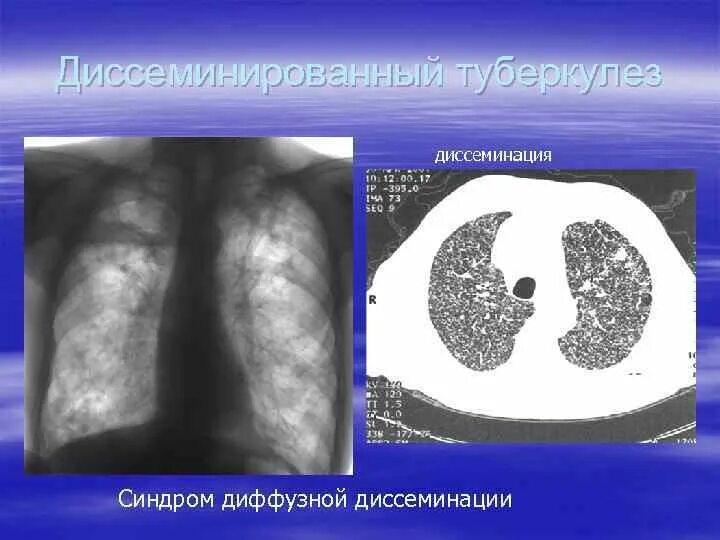

Синдром диффузной